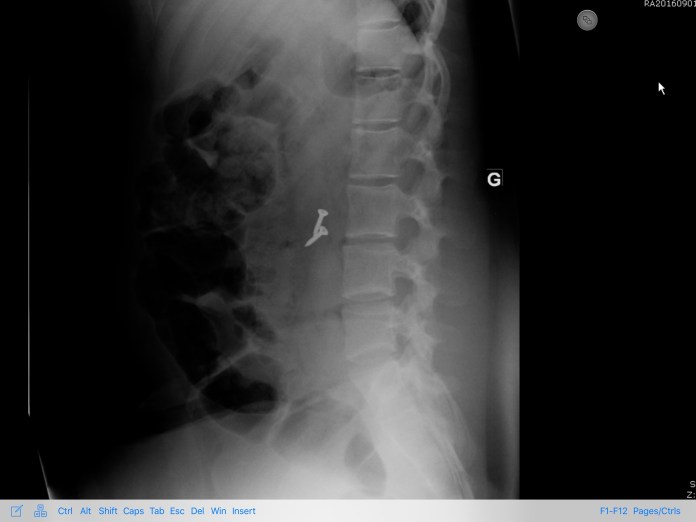

Conseils du doc vol. 7

👉🏿 Enfants:  il ne faut pas confondre les clous, les vis, les clés USB avec des sucettes.

👉🏿 Parents: rangez bien vos boite à outils…

À ce rythme là je vais finir par ouvrir une quincaillerie 😂

🔨🛠⛏🗝